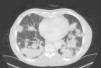

Un varón de 80 años de edad, exfumador, acudió por disnea y manifestaciones sistémicas (astenia, anorexia y pérdida de peso) de unos pocos meses de evolución. La exploración física y los análisis de laboratorio no mostraron alteraciones significativas. La radiografía de tórax mostró múltiples lesiones nodulares dispersas por todos los campos pulmonares. La TC toracoabdominal mostró lesiones pulmonares nodulares dispersas, de contornos lobulados y sin calcificaciones, en ambos pulmones (fig. 1). La broncoscopia no mostró microorganismos ni células malignas. La PET-TC llegó a la conclusión de que algunas lesiones de ambos pulmones tenían una afinidad significativamente mayor por la FDG y que no había signos de lesiones de captación elevada en ningún otro lugar del organismo. Las pruebas de la función pulmonar mostraron una obstrucción moderada de las vías aéreas. Las biopsias transtorácica y transbronquial mostraron células amorfas con características de amiloide. Después de 24 meses, el paciente mantiene un buen estado clínico y está siendo tratado con un broncodilatador de acción prolongada (LABA) inhalado y un corticosteroide inhalado.

Radiológicamente, la amiloidosis pulmonar parenquimatosa nodular primaria se manifiesta por nódulos únicos o múltiples en cualquier lóbulo, y debe tenerse en cuenta en el diagnóstico diferencial de las neoplasias pulmonares primarias o metastásicas, la tuberculosis pulmonar, la sarcoidosis pulmonar y las enfermedades del tejido conjuntivo2. Los nódulos son generalmente periféricos y subpleurales y presentan 4 características típicas en la TC: contornos bien delimitados y lobulados, calcificación, a menudo central o de patrón irregular en el interior del nódulo, con múltiples formas y tamaños y crecimiento lento, a menudo a lo largo de años, sin remisión3.